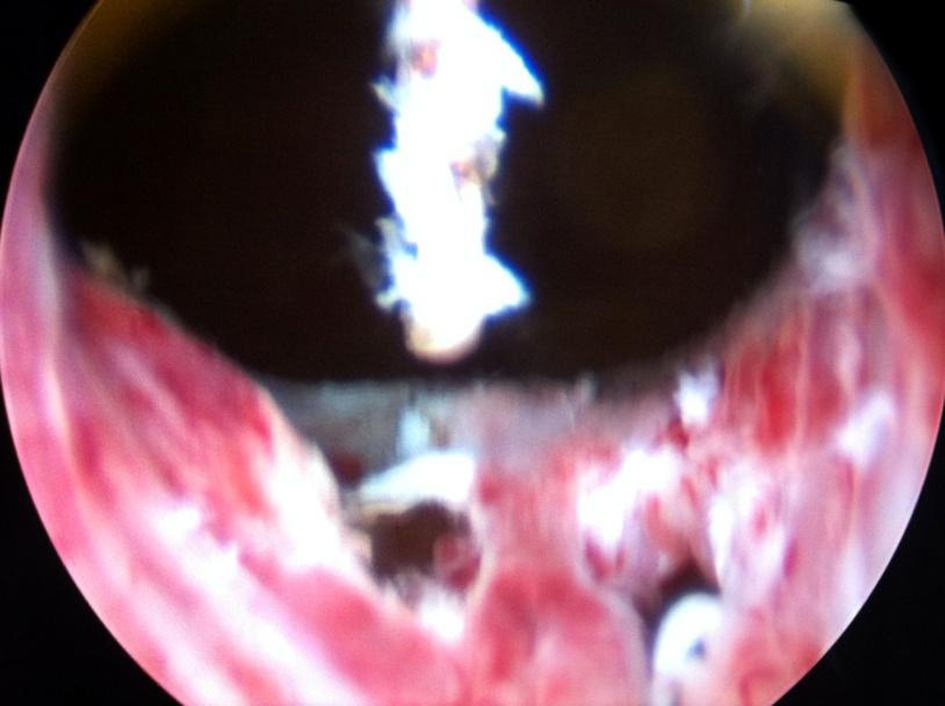

Transurethral incision of the right ureterocele was done by using a resectoscope with Collins hot knife (Fig. 6). A longitudinal incision was given extending from the bladder neck to the stenosed opening of right ureterocele to improve drainage of the right solitary functioning kidney. Right double J stent was placed. Subsequently renal functions improved and his creatinine came down to 1.6 mg%. He is planned for left nephroureterectomy and if necessary right ureteric re-implantation as a secondary major surgery in the follow-up period.

![]() Click for large image | Figure 6. Right ureterocele incised with Collins hot knife. |